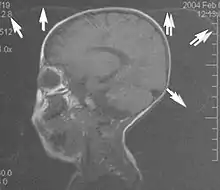

Metal artifacts

Metal artifacts occur at interfaces of tissues with different magnetic susceptibilities, which cause local magnetic fields to distort the external magnetic field. This distortion changes the precession frequency in the tissue leading to spatial mismapping of information. The degree of distortion depends on the type of metal (stainless steel having a greater distorting effect than titanium alloy), the type of interface (most striking effect at soft tissue-metal interfaces), pulse sequence and imaging parameters. Metal artifacts are caused by external ferromagnetics such as cobalt containing make-up, internal ferromagnetics such as surgical clips, spinal hardware and other orthopaedic devices, and in some cases, metallic objects swallowed by people with pica.[3] Manifestation of these artifacts is variable, including total signal loss, peripheral high signal and image distortion (Figs 3 and 4).[1] Reduction of these artifacts can be attempted by orientating the long axis of an implant or device parallel to the long axis of the external magnetic field, possible with mobile extremity imaging and an open magnet. Further methods used are choosing the appropriate frequency encoding direction, since metal artifacts are most pronounced in this direction, using smaller voxel sizes, fast imaging sequences, increased readout bandwidth and avoiding gradient-echo imaging when metal is present. A technique called MARS (metal artifact reduction sequence) applies an additional gradient, along the slice select gradient at the time the frequency encoding gradient is applied. ==Signal processing dependent artifacts== The ways in which the data are sampled, processed and mapped out on the image matrix manifest these artifacts.[1]